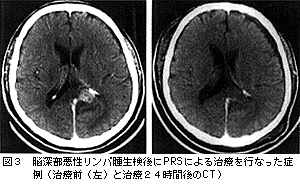

PRSは手術で脳腫瘍を切除した際,残存する腫瘍に対して術中照射として使用する方法と,脳深部の腫瘍等に対して定位的生検を行なう際に,組織診断確認後に生検針と代えて局所放射線治療を行なう2通りの治療法がある。照射計画は,術前にコンピュータを用いて線量分布と線量をあらかじめ測定,決定しておく。照射線量は,腫瘍の周辺線量で定める。腫瘍の直径によって照射時間が異なってくるが,直径1cm程度の小さい腫瘍では数分,直径が3cm程度では数十分間の照射が必要になる。本法を用いて治療した症例を図3に示した。

本例は視床部に近い腫瘍で,手術による摘出では重大な神経症候が発生する部位に存在した。生検で悪性リンパ腫と診断されたので,その際に局所に7分間,周辺線量10GyのPRSによる治療を行なった。悪性リンパ腫は放射線感受性が高い腫瘍であるが,本例では24時間後のCTでは腫瘍がすでに消失していた。